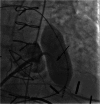

There is a growing appreciation for the adverse long-term impact of right-sided valvular dysfunction in patients with congenital heart disease. Although right-sided valvular stenosis and/or regurgitation is often better tolerated than left-sided valvular dysfunction in the short and intermediate term, the long-term consequences are numerous and include, but are not limited to, arrhythmias, heart failure, and multi-organ dysfunction. Surgical right-sided valve interventions have been performed for many decades, but the comorbidities associated with multiple surgeries are a concern. Transcatheter right-sided valve replacement is safe and effective and is being performed at an increasing number of centers around the world. It offers an alternative to traditional surgical techniques and may potentially alter the decision making process whereby valvular replacement is performed prior to the development of long-term sequelae of right-sided valvular dysfunction.